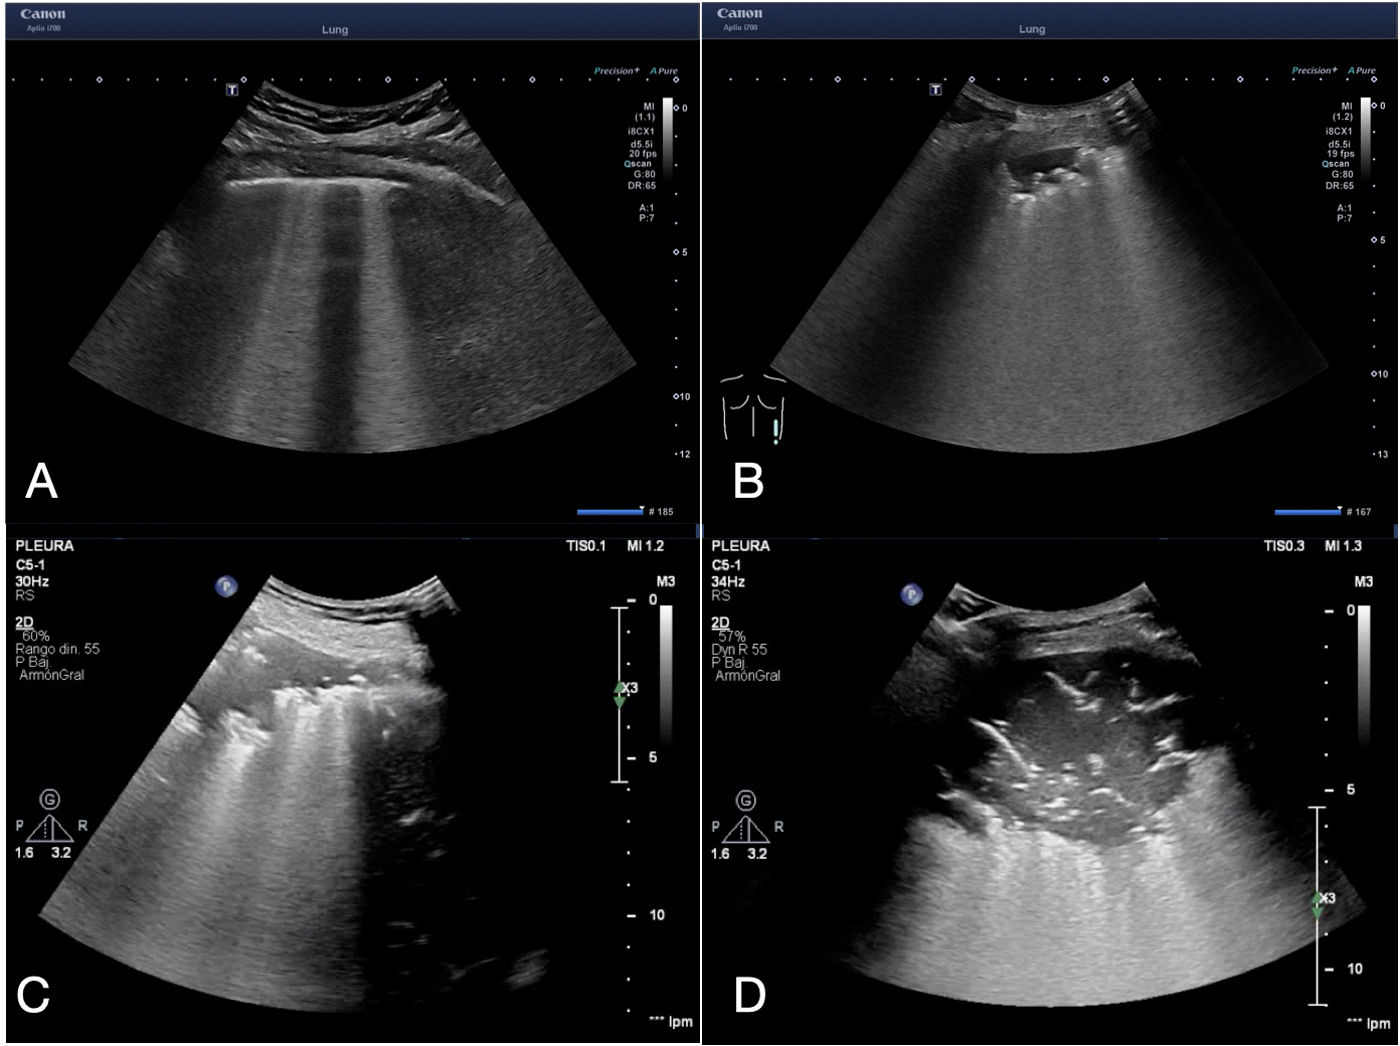

Más datosPoint-of-care ultrasound (POCUS) is a rapid bedside imaging modality available to clinicians for the diagnosis of pleuropulmonary infections. Compared with chest radiography, POCUS is more sensitive in identifying pneumonia and its complications (parapneumonic pleural effusions, necrosis, and abscesses). The most common sonographic features of pneumonia are consolidation (with irregular margins and dynamic air bronchograms), B-lines, and pleural effusion. POCUS also has prognostic applications, for example, to determine the severity of COVID-19 pneumonia or to predict residual pleural thickening in a tuberculous effusion. Finally, the presence of a complex septated ultrasound pattern in the context of pleural infection is indicative of the need for drainage, which is performed using a thoracostomy tube and instillation of intrapleural enzyme therapy.

El ultrasonido en el punto de atención (point-of-care ultrasound [POCUS]) es una modalidad de imagen rápida y disponible a la cabecera del paciente para el diagnóstico de las infecciones pleuropulmonares. En comparación con la radiografía de tórax, el POCUS es más sensible para identificar la neumonía y sus complicaciones (derrame pleural paraneumónico, necrosis y abscesos). Los signos sonográficos más comunes de la neumonía son la consolidación (con márgenes irregulares y broncograma aéreo dinámico), las líneas B y el derrame pleural. El POCUS también tiene implicaciones pronósticas, por ejemplo, para determinar la gravedad de una neumonía por COVID-19 o predecir el engrosamiento pleural residual en un derrame tuberculoso. Por último, la presencia de un patrón ecográfico complejo septado en el contexto de una infección pleural es indicativo de la necesidad de un drenaje, que se realiza mediante un tubo de toracostomía y la instilación de terapia enzimática intrapleural.